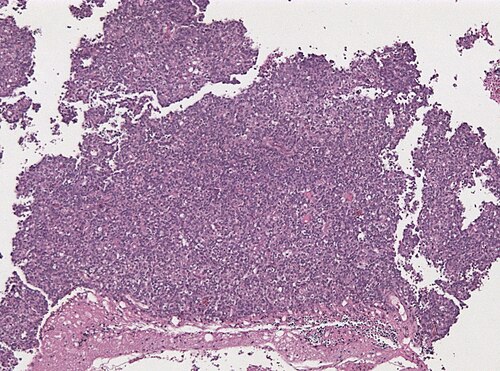

8 month old drowsy child, emergency surgery

Site

Cerebellum

Low magnification. H&E stain.

A malignant small round blue tumor in the cerebellum. We need some special stains.

Atypical teratoid / rhabdoid tumor, WHO grade IV